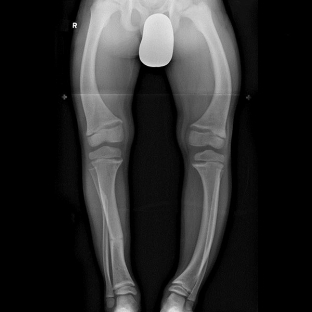

Instrumental research methods are also widely used to diagnose osteomalacia syndrome. With the help of a histomorphological study, it is possible to assess the rate of calcification and bone formation. For this, the double tetracycline label method is used, according to the results of which, in osteomalacia, the distance decreases between two tetracycline labels, and a non-mineralized matrix appears. X-ray studies are the most informative in osteomalacia syndrome. Important signs of osteomalacia are changes in the vertebral bodies: blurring of their patterns, concavity of the edges, sometimes compression fractures.

A characteristic radiological symptom of osteomalacia is the detection of Looser's zones – fissures or narrow lines that transmit x-rays, have sclerotic margins, and are perpendicular to the cortical margin of the bone.